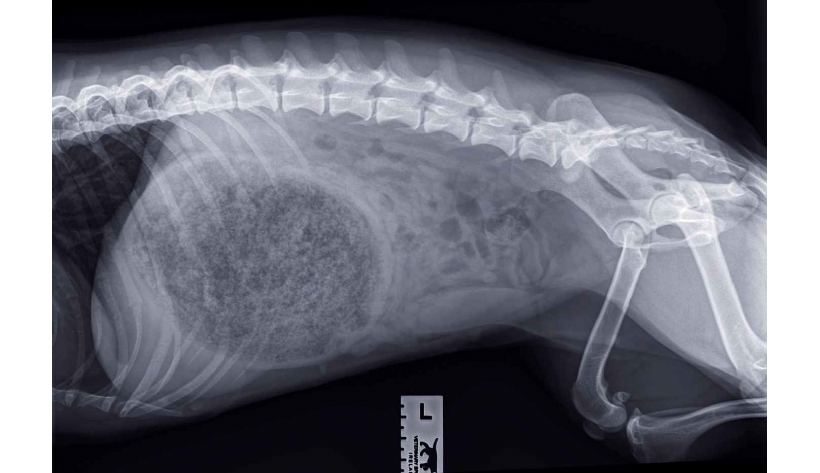

Photo n° 1B : Radiographie abdominale de profil.

Des radiographies abdominales orthogonales (photos 1A et 1B) sont réalisées.

Les radiographies abdominales mettent en évidence une silhouette stomacale hétérogène distendue avec un pattern tacheté/moucheté en son sein, un effet de masse en région crâniale est observé (photo n° 2).

Associées aux antécédents cliniques, elles suggèrent la présence d'un cyano-bézoard gastrique, formé à la suite de l'ingestion de colle, entraînant une obstruction du pylore et du cardia.